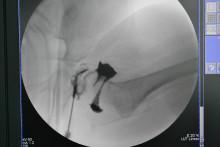

术中关节造影